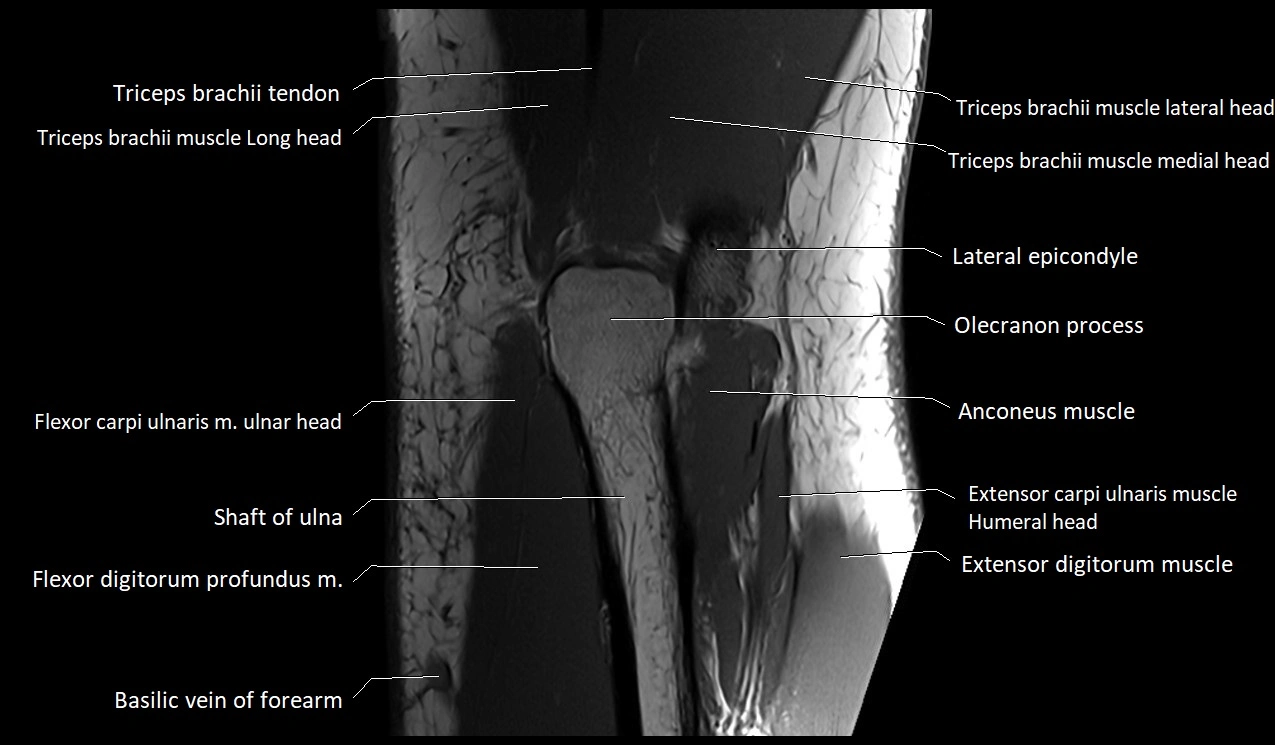

MRI image

image